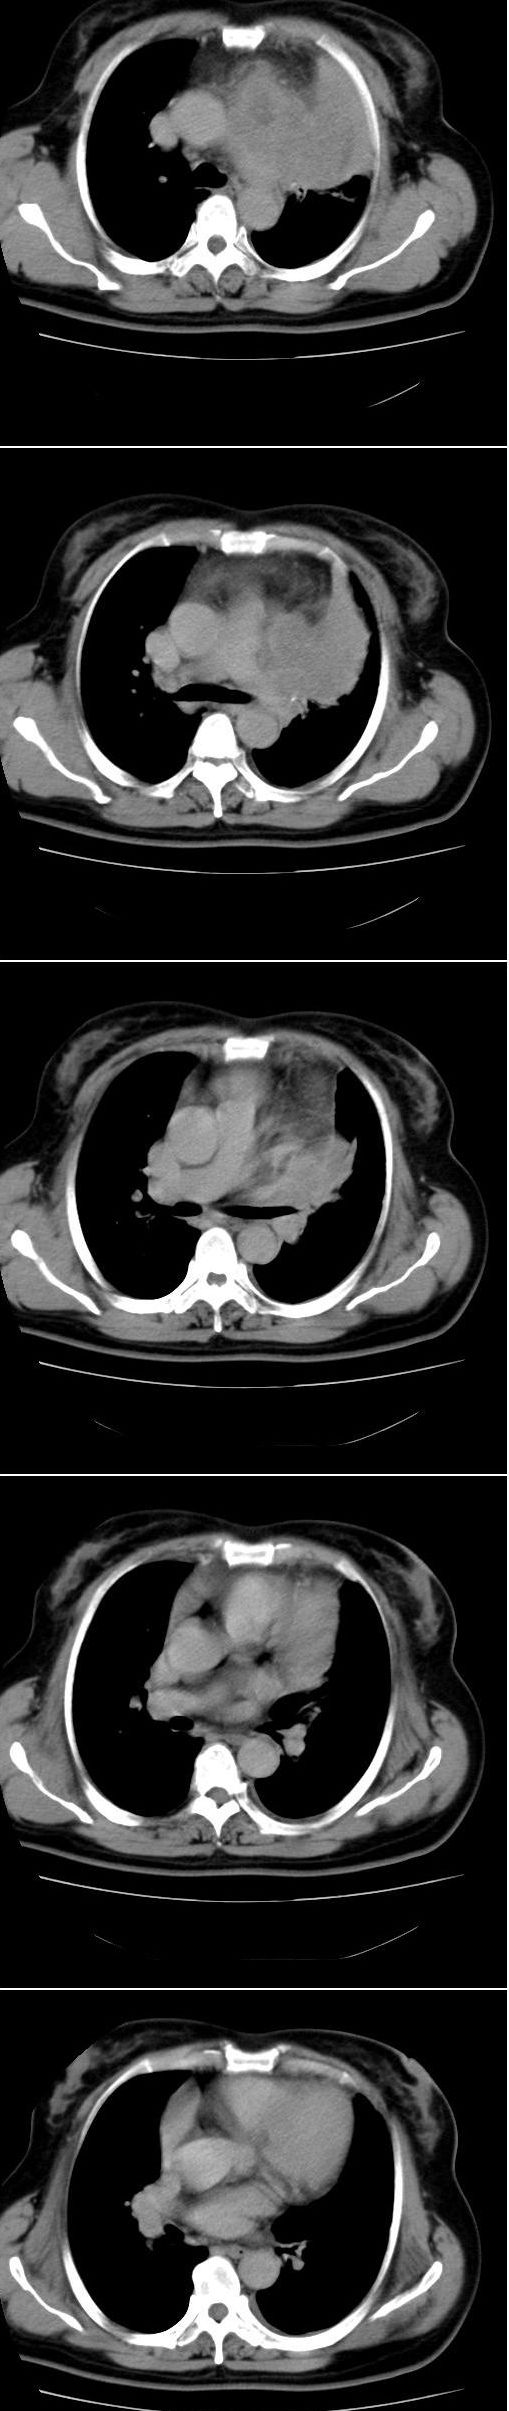

标题: CT13028:女,56岁。咳嗽、气促一月,咳血一周。CT值增加约30 [打印本页]

标题: CT13028:女,56岁。咳嗽、气促一月,咳血一周。CT值增加约30

左上肺肿块伴阻塞性改变,考虑肺癌可能大

感觉病灶主要来源于前上纵隔,向周围浸润,考虑为侵袭性胸腺瘤。

考虑左上肺癌(周围型)伴左肺门及纵隔转移(主肺动脉窗旁病灶可能为肿大并坏死的淋巴结),不除外纵隔型肺癌

软组织肿块,应该有肺不张(因为左膈及脾脏\\胃抬高明显):考虑中央ca

支持纵隔旁型肺癌伴主动脉弓\\主肺动脉及左侧头壁动脉受侵.

考虑左肺中心性肺癌并纵隔淋巴结转移,累及左肺动脉及左侧头臂静脉.但不除外纵隔恶性肿瘤累及肺组织.

考虑左肺中心性肺癌并纵隔淋巴结转移,纵隔恶性肿瘤累及肺组织的可能性小,因为后者一般不会导致横膈上抬。

考虑左侧中央型肺癌伴左肺上叶肺不张及前纵隔淋巴转移。

1)考虑为:左肺上叶中心型肺癌伴左肺上叶阻塞性肺炎、节段性肺不张,左肺门及纵隔淋巴结转移。2)左侧少量胸腔积液。